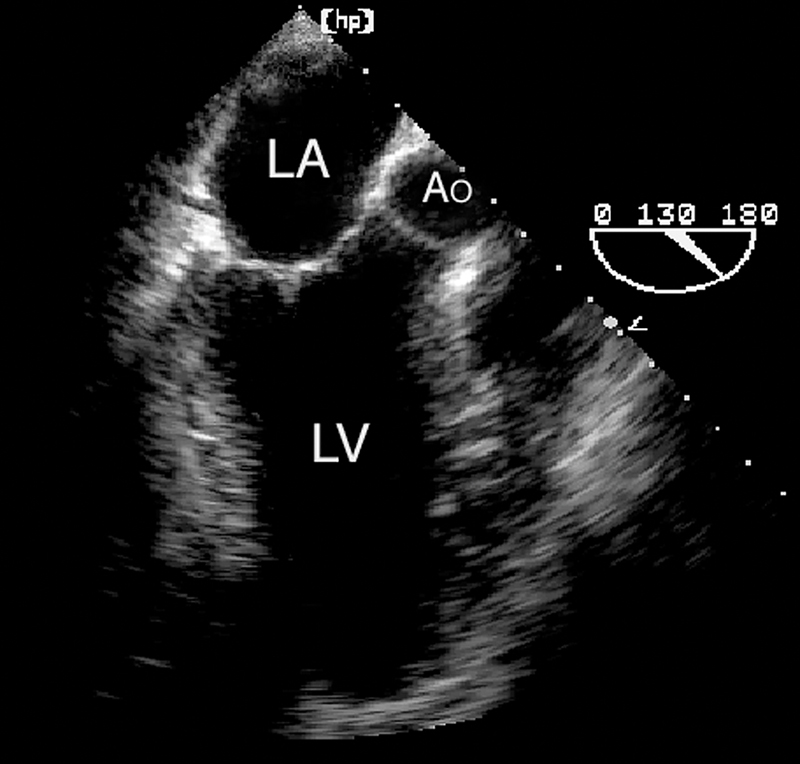

فحوصات تشخيصية لبعض امراض القلب والشرايين التاجية